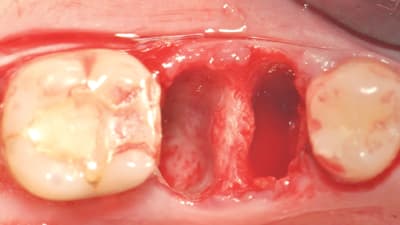

Clinical Technique Review Implantology Osseodensification Effective for Immediate Molar Replacement By Rodrigo Neiva, DDS, Salah Huwais, DDS, Samvel Bleyan, DDS July 15, 2022 13 min read